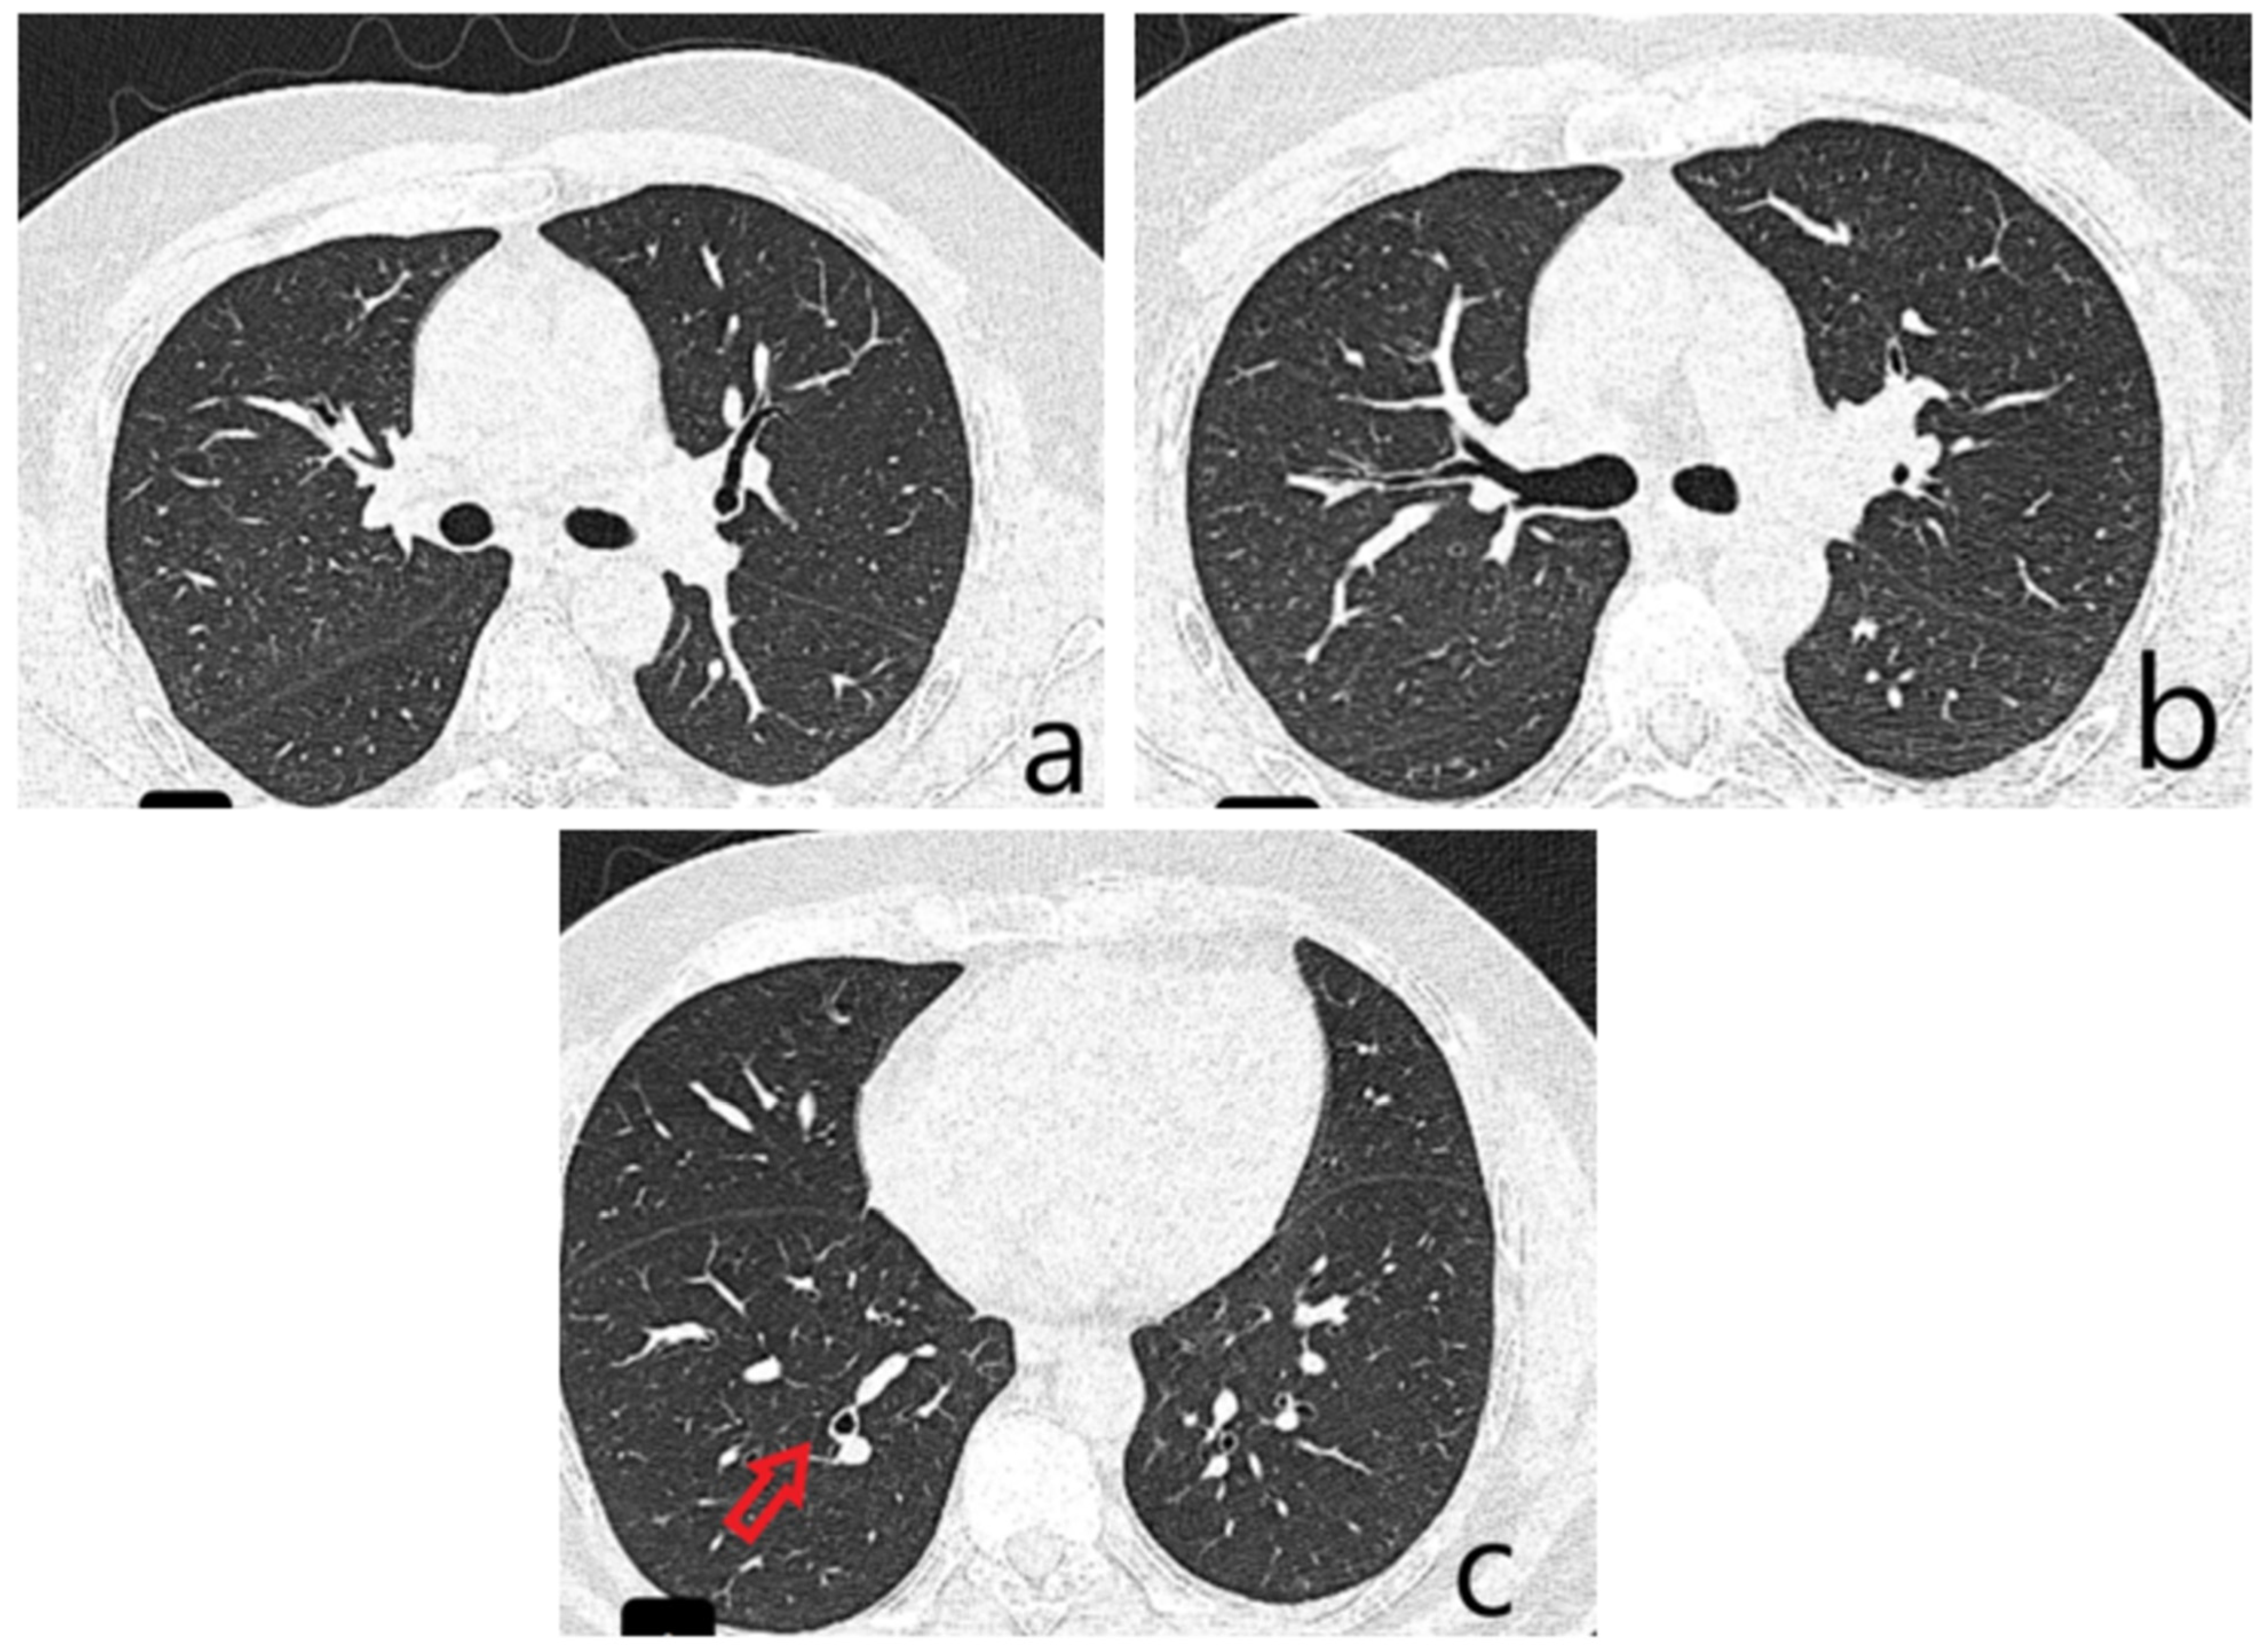

Figure 2. A Chest CT demonstrated solid and subsolid pseudonodular and micronodular infiltrates in the right upper lobe (RUL), showing a tendency to confluence ((a), green arrows) and areas with a “tree-in-bud” appearance ((b), green arrows) on a background of ground-glass opacity. These findings were initially interpreted as consistent with an infectious process, although serial sputum cultures yielded no identifiable bacterial pathogen. Based on the clinical and imaging profile, a diagnosis of right upper-lobe pneumonia was made, and empirical ceftriaxone therapy was initiated, resulting in resolution of fever, remission of the dry irritative cough, and normalization of inflammatory markers. The CT scan also revealed cylindrical bronchiectasis with wall thickening in the right lower lobe ((c), yellow arrow). Pulmonary function testing showed moderate restrictive ventilatory dysfunction (forced vital capacity 66% of predicted) without significant bronchodilator response, and normal DLCO. Given the inconclusive microbiological results, a fiberoptic bronchoscopy was performed to further asses the airway mucosa and rule out endobronchial lesions.